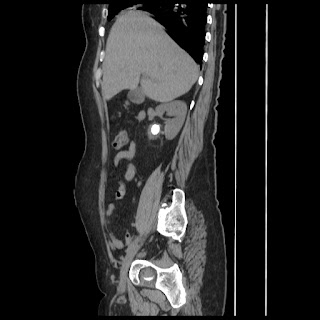

A CT abdomen revealed a left adrenal cortical tumor.

CT images: